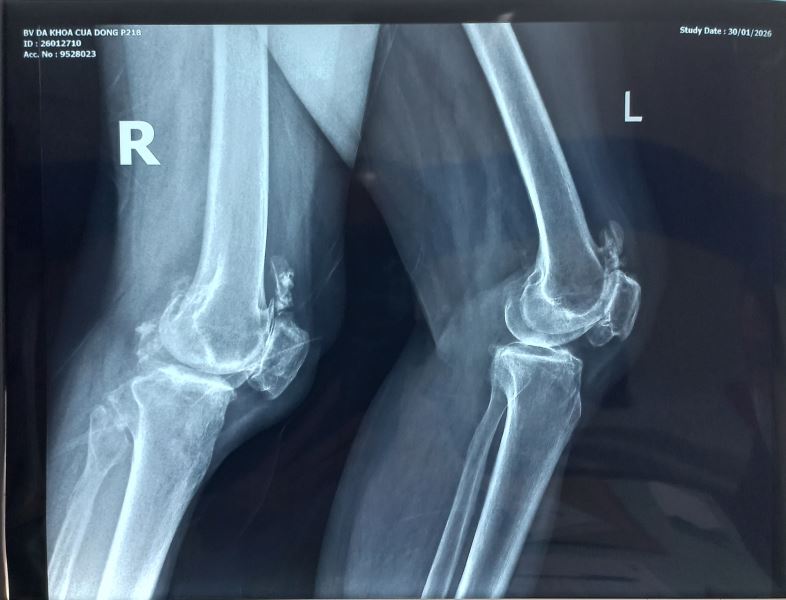

Chụp X-quang cho hình ảnh dưới đây.

Chúng tôi nghĩ đến bệnh Synovial Osteochondromatosis một loại bệnh hiếm gặp và cho bệnh chân chụp MRI khớp cho kết quả sau: